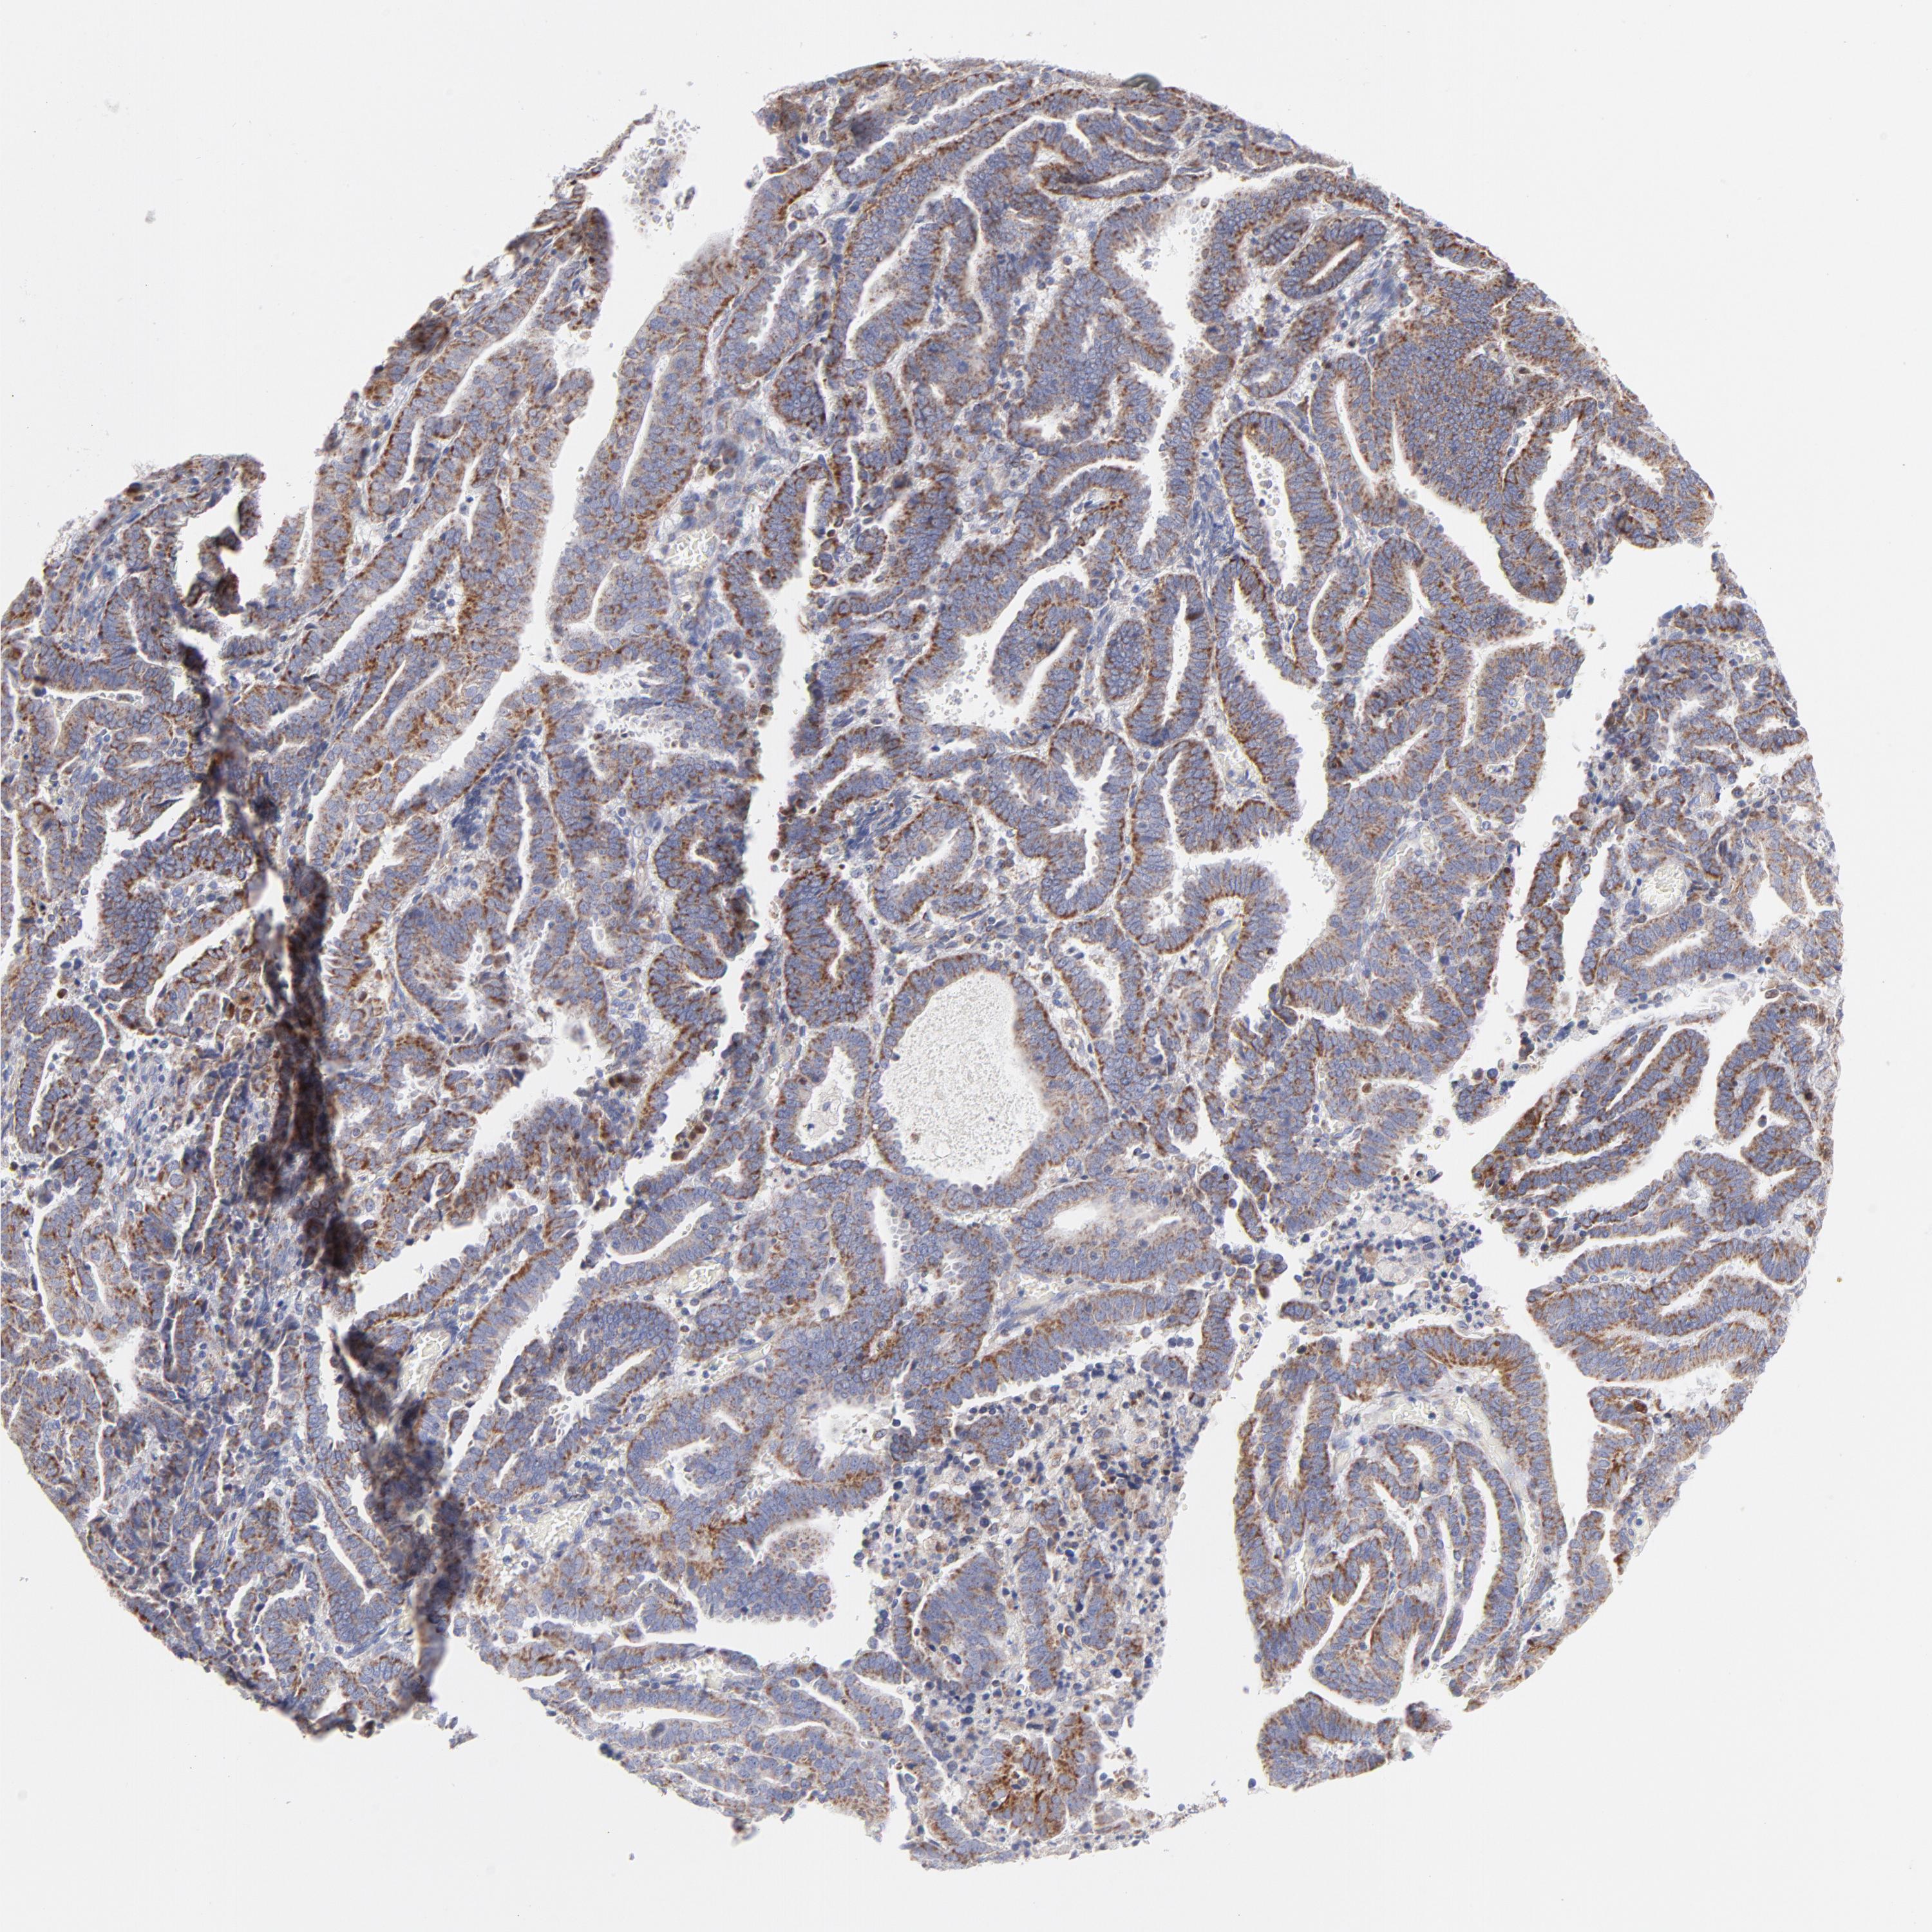

ENDOMETRIAL CANCER - Protein expressioni

A mouse-over function shows sample information and annotation data. Click on an image to view it in a full screen mode. Samples can be filtered based on level of antibody staining by selecting one or several of the following categories: high, medium, low and not detected. The assay and annotation is described here.

Note that samples used for immunohistochemistry by the Human Protein Atlas do not correspond to samples in the TCGA dataset.

Antibody stainingi

Antibody staining in the annotated cell types in the current human tissue is reported as not detected, low, medium, or high, based on conventional immunohistochemistry profiling in selected tissues. This score is based on the combination of the staining intensity and fraction of stained cells.

Each image is clickable and will lead to virtual microscopy that enables deeper exploration of all samples and also displays staining intensity scores, fraction scores and subcellular localization as well as patient and tissue information for each sample.

Antibody HPA003628

Staining

High

Medium

Low

Not detected

Intensity

Strong

Moderate

Weak

Negative

Quantity

>75%

75%-25%

<25%

None

Location

Nuclear

Cytoplasmic/membranous

Cytoplasmic/membranous,nuclear